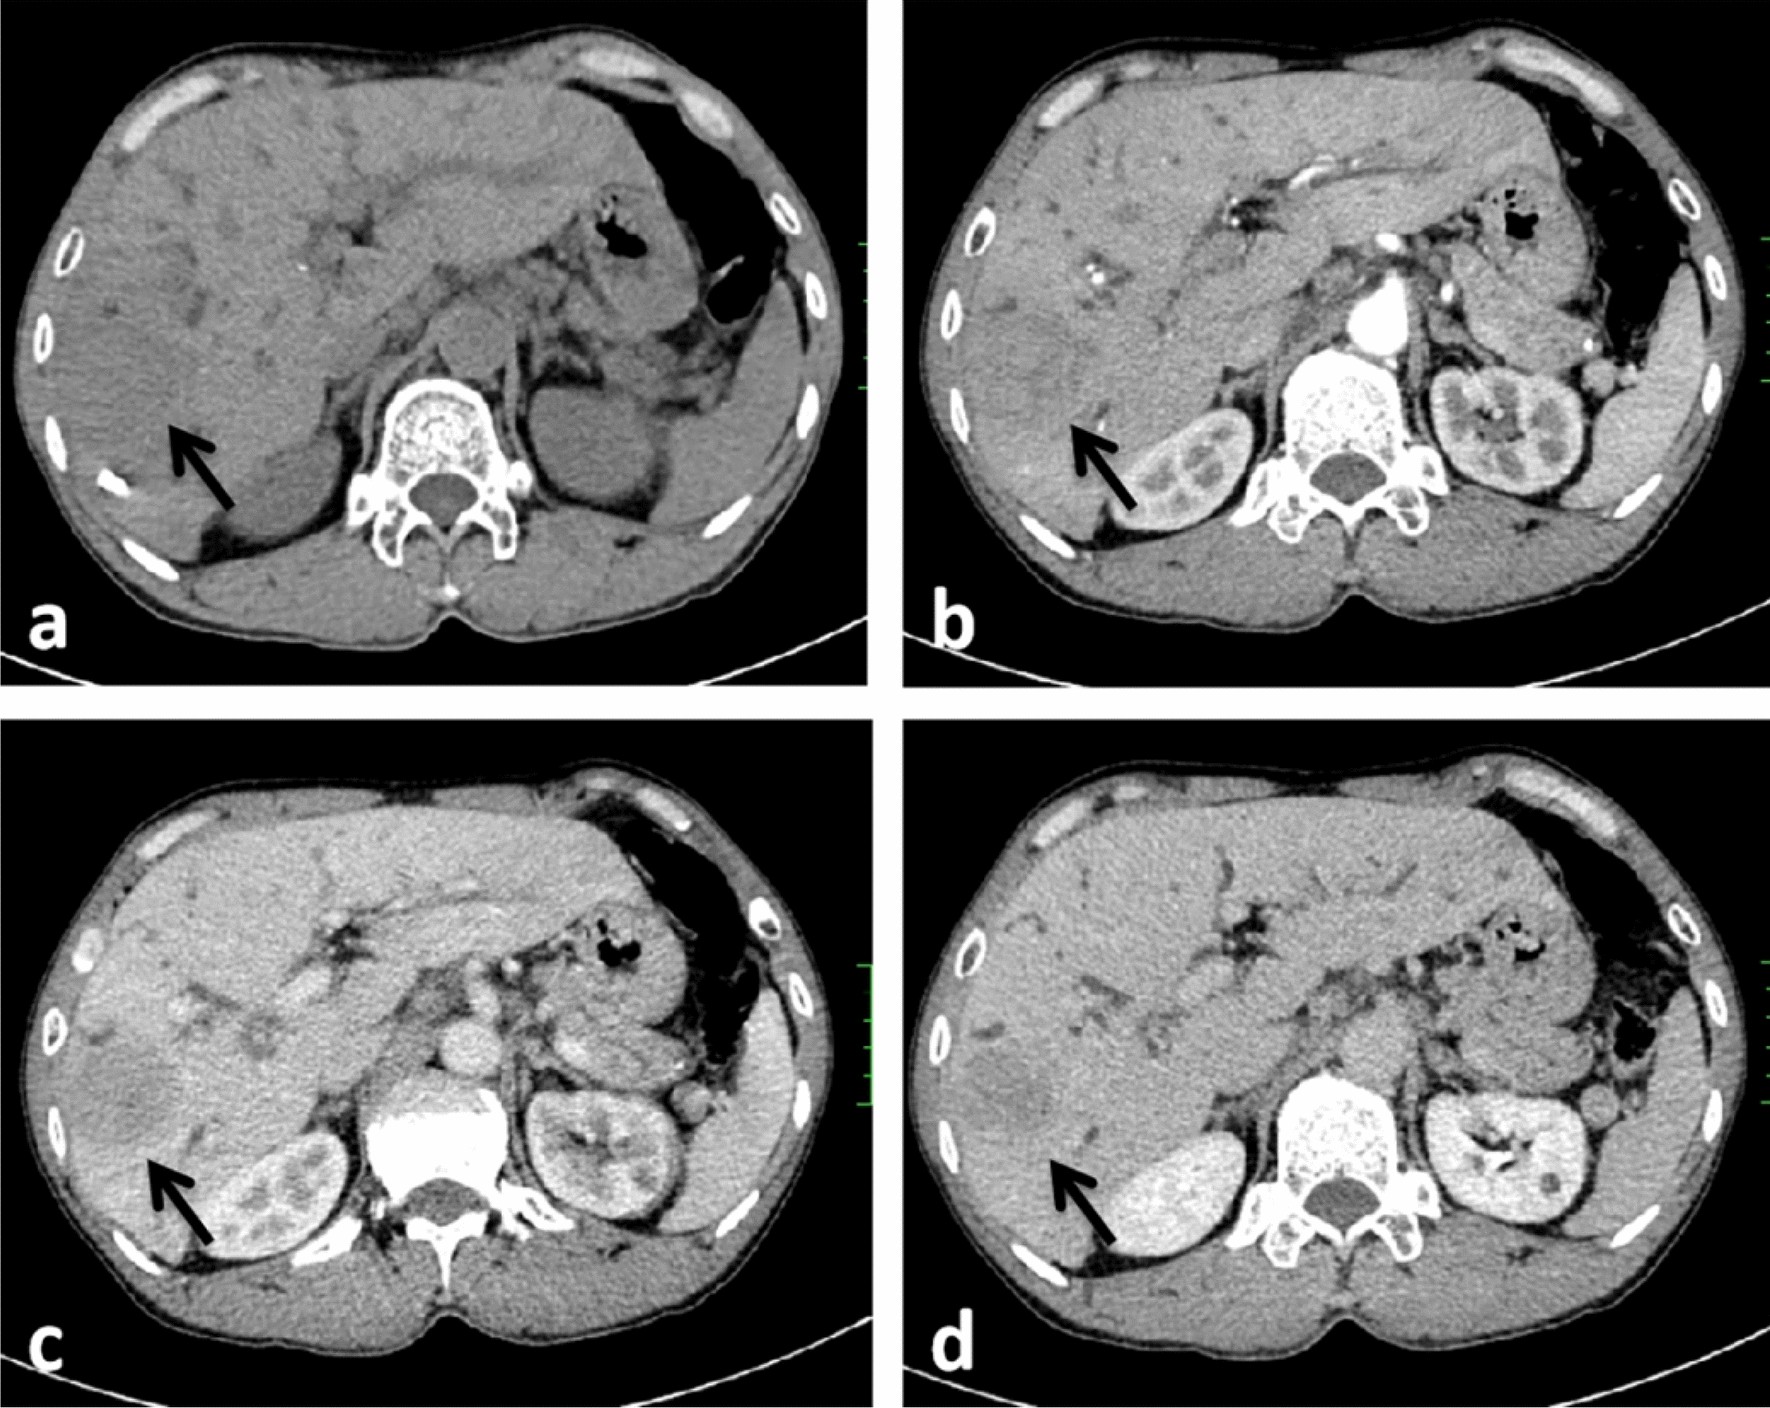

Figure 3

CT images in a 54-year-old HBV-negetive man with ICC confirmed by surgical resection, positive for schistosoma hepatica, AFP 6.56 ng/ml, CA19-9 < 2.00 U/ml, and its enhancement pattern was categorised as type II. Precontrast image (a) showed a solitary tumor (arrow) in segment VI of the liver; arterial phase (b), portal phase (c) and delayed phase (d) showed progressive hypoenhancement; portal phase (c) showed dilated intrahepatic bile ducts.